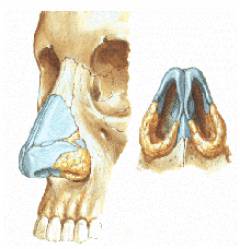

Существует наружный нос, выступающий над лицевым черепом, и носовая полость внутри. Вход в носовую полость образует грушевидное отверстие.

Структура наружного носа:

- Передняя часть формируется из хрящей, которые мягкие и легко деформируются, но быстро восстанавливают форму.

- Костная структура состоит из отростков лобной и верхнечелюстной костей, а также парных носовых костей. Повреждение костной части может привести к перелому носа.

Носовая полость делится на преддверие (наружная часть), дыхательную часть (нижняя часть, по которой проходит воздух) и обонятельную часть (верхняя часть, где находятся нервные окончания, отвечающие за восприятие запахов). Она соединяется с придаточными пазухами – полостями в лобной, верхнечелюстной (гайморовы пазухи) и решетчатой костях. При переломах носа возможно повреждение этих пазух.

Носовая полость разделена на две половины носовой перегородкой, состоящей из хрящевой и костной частей. С каждой стороны носовой полости располагаются три мелкие косточки – верхняя, средняя и нижняя носовые раковины.